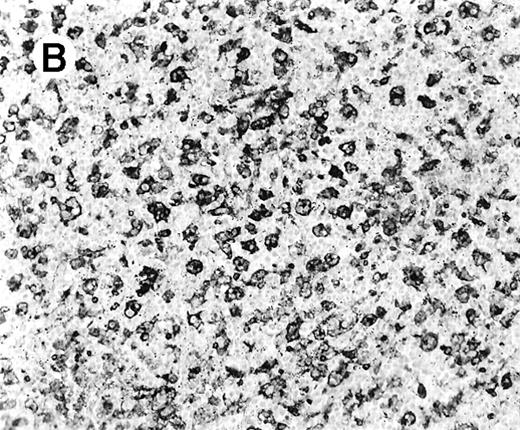

All cases showed essentially similar histologic findings in the liver and spleen. The splenic white pulp was inconspicuous to markedly depleted, whereas the sinusoids showed a prominent lymphoid infiltration (Figure 1A). There was striking hemophagocytosis within the splenic sinusoids (Figure 1B). The infiltrating lymphocytes were small and lacked significant cytologic atypia (Figure 1B). Immunoblasts and plasma cells were not prominent. The liver had prominent portal as well as sinusoidal infiltrates of small lymphocytes morphologically identical to those noted in the spleen (Figure 2). There was intracellular and intracanalicular cholestasis, steatosis, and focal necrosis. Hemophagocytosis was present within the sinusoids. In case 5, the spleen showed extensive areas of necrosis mainly in the perifollicular and periarteriolar lymphoid sheaths of the white pulp with the presence of immunoblasts reminiscent of IM.

(A) Section of spleen from case 2 shows depletion of white pulp and prominent sinusoidal small lymphoid infiltrates (hematoxylin and eosin, × 200). (B) The lymphocytes lack significant cytologic atypia. There is marked hemophagocytosis (hematoxylin and eosin, × 600).